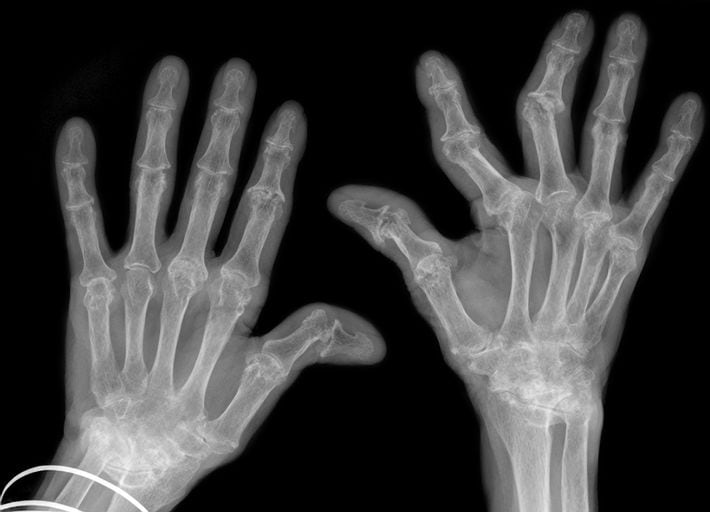

高市首相「手痛ドタキャン騒動」を現役医師が時系列検証…プロが「あのテーピング」に抱いた強烈な違和感

※写真はイメージです